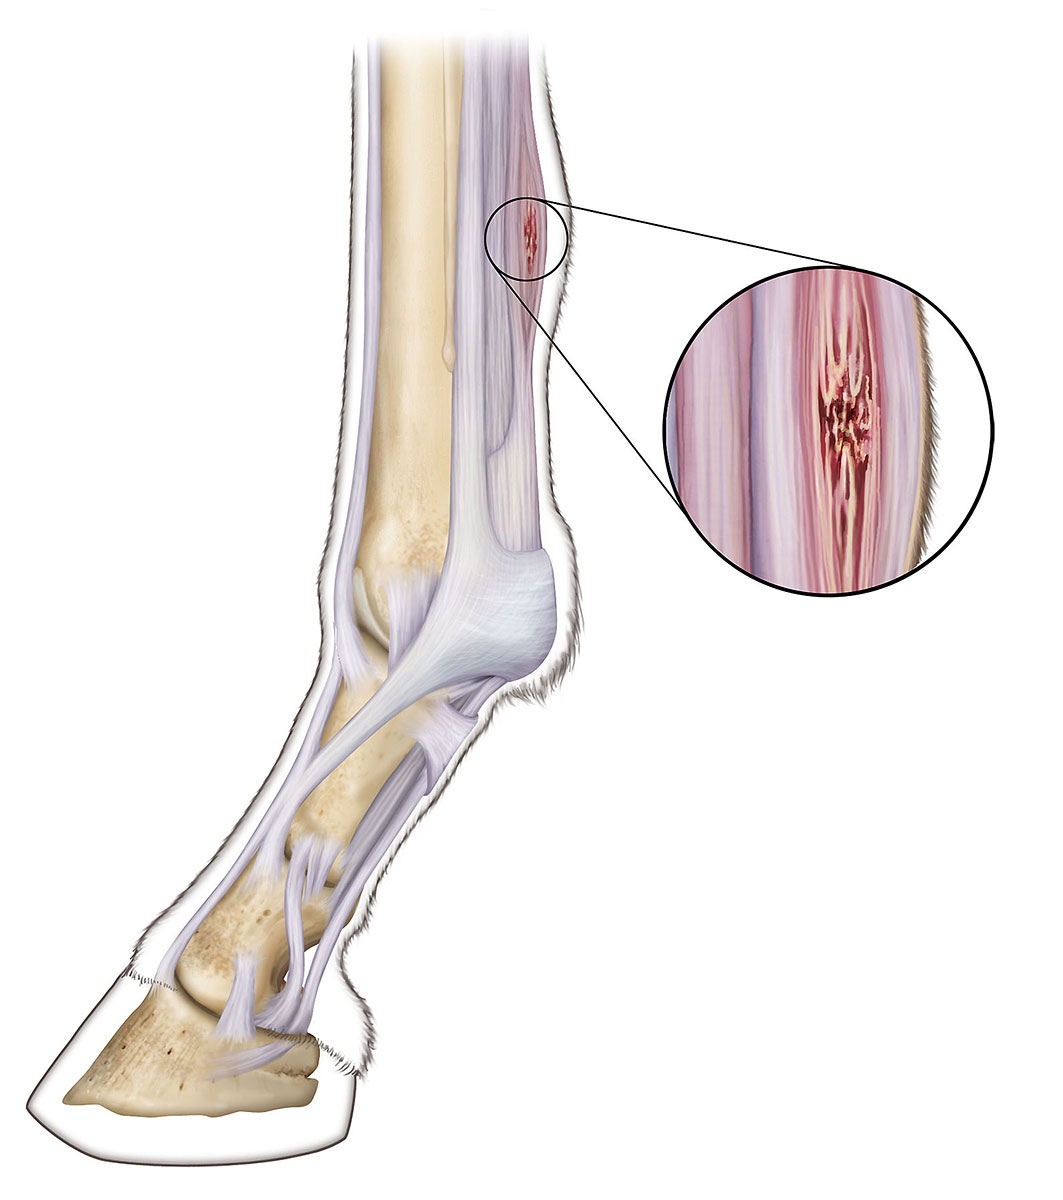

Scratching the surface of tendon injury and rehabilitation